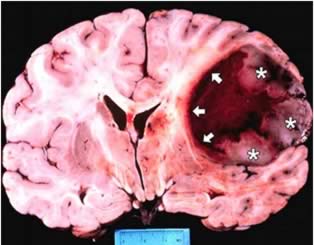

La nuova ricerca è la prima a mostrare un effetto positivo della combinazione di THC e CBD e radioterapia, sul cancro al cervello. I tumori nel cervello dei topi sottoposti a trattamento, sono stati drasticamente rallentati quando THC / CBD sono stati utilizzati con la la radioterapia.

Il Dr. Wai Liu, Senior Research Fellow e ricercatore responsabile del progetto, ha dichiarato: “I risultati sono estremamente eccitanti. I tumori sono stati trattati in una varietà di modi: con nessun trattamento, solo son cannabinoidi, solo con la radioterapia o con i cannabinoidi e radioterapia, contemporaneamente.

“Quelli trattati sia con radioterapia che cannabinoidi, hanno mostrato risultati più vantaggiosi e una drastica riduzione delle dimensioni. In alcuni casi, i tumori sono efficacemente scomparsi negli animali. Questi risultati sono l’ auspicio di ulteriori ricerche sull’uomo, in futuro”.

“I benefici degli elementi della cannabis erano conosciuti da tempo, ma la drastica riduzione dei tumori cerebrali se utilizzati con la radioterapia è qualcosa di nuovo e potrebbe rivelarsi promettente per i pazienti malati di cancro al cervello, in futuro”.